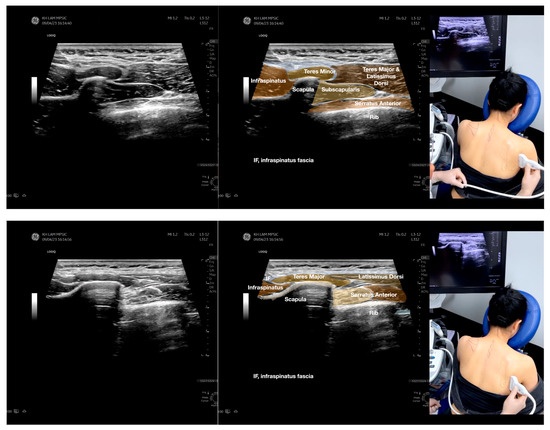

Figure 5.

Sonoanatomy of scanning the infraspinatus fascia in the sagittal plane from the rhomboid minor laterally, then back to the rhomboid major. The step-by-step scanning techniques of the structures illustrated in this figure have been shown in Video S9. Available online: https://www.dropbox.com/s/gu9hhrdq9erin6n/Figure%205.docx?dl=0 (accessed on 1 January 2023).